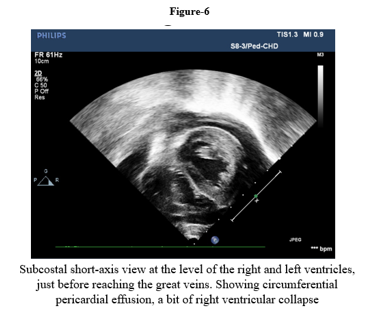

We report a four-month-old girl who presented in sudden cardiorespiratory collapse to illustrate an uncommon cardiac first sign of MTO1-related disease. The infant arrived hypotensive and obtunded with severe metabolic acidosis (pH 6.59; lactate 29 mmol/L). Chest radiograph showed cardiomegaly and bedside echocardiography revealed a large circumferential pericardial effusion producing compression of the right heart together with concentric left-ventricular hypertrophy. Emergency pericardiocentesis drained 120 mL of serous fluid and produced only transient improvement; over a prolonged PICU stay she had recurrent sterile effusions, four failed extubation attempts, refractory lactic acidosis, renal dysfunction and progressive bradycardia. Whole-exome sequencing identified a homozygous pathogenic MTO1 variant (NM_012123.4:c.1232C>T; p. Thr411Ile); both parents were heterozygous carriers. The family history included consanguinity and a sibling who died in early infancy after a similar illness. Despite maximal supportive care, she died on day 40 from cardiogenic shock and multiorgan failure. The case highlights that recurrent sterile pericardial effusion in an infant with hypertrophy and marked hyperlactatemia should prompt consideration of an underlying mitochondrial (MTO1-related) disorder and early genetic testing to guide counselling

This case illustrates tamponade as the initial cardiac manifestation of COXPD10. In infants, large effusions leading to tamponade should typically give rise to strong concerns for an infected, malignant, autoimmune, or post-surgical cause. Sterile recurrent effusions in addition to hypertrophic cardiomyopathy, in our patient, were suggestive of a metabolic cardiomyopathy.